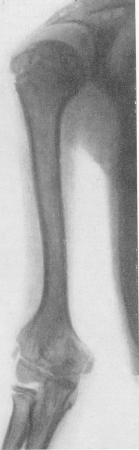

Fig. 273. Osteocondrodystrofia la un băiat de 13 ani cu o imagine clinică și radiologică tipică a bolii. Radiografia humerusului.

Fața pacienților cu osteocondro-dystrofie nu se evidențiază, este normal, exprimând în mod normal sau ocazional doar câteva dezvoltări mentale întârziate. Ambele sexe sunt afectate cu aceeași frecvență. Din partea diferitelor sisteme de anumite tulburări cu osteocondrodystrofia nedezvoltată nu se întâmplă. În cazuri rare, indicați o piele groasă neelastică, iar carcasa poate ajunge la sclerodermie, ceea ce face dificilă deplasarea degetelor - cu articulații libere! Uneori părul este uscat, rigid. Se menționează de asemenea tulburări foarte rare de la ochi - opacități corneene, atrofie optică, pierderea progresivă a vederii. Sistemul endocrin nu prezintă abateri evidente față de normă. Până în prezent, sistemul nervos nu a fost supus nici unui studiu special de nimeni. Etiologia osteochondrodystrofiei și a patogenezei sale este un mister și nu vom enumera numeroasele ipoteze care au fost făcute în legătură cu aceasta. Esența bolii - aceasta este o eroare innascuta profund de transformare proceselor hryasha în țesutul osos, adică un fel de encondrală inferioritate, dar nu osificare periostal ... Sub microscop, modificările degenerative ale sistemului enchondral cartilaginos nu reprezintă nimic specific. În conformitate cu toate aceste date, există o imagine bogată a imaginii roentgenologice a osteochondrodystrofiei. Toate oasele scheletului sunt la un mic grad de fiară. Diafiza oaselor tubulare mari (figurile 261, D) nu reprezintă modificări brute. Ele sunt puțin mai groase decât de obicei. Prin urmare, ele par mai scurte decât în mod normal. Cu toate acestea, uneori sunt la pacienții noștri și sunt de fapt scurtați, mai ales la nivelul oaselor femurale și humerale în comparație cu tibia și antebrațul. Când acest strat diafiză cortical bit este subțiat, canalul medular este larg, iar numai liniile au crescut cortexul încărcare densă și groasă (Fig. 273). Capetele articulațiilor oaselor sunt lărgite. Epifize de configurație neregulată, stângace, mărite în diametru, dar aplatizate, unghiulare.